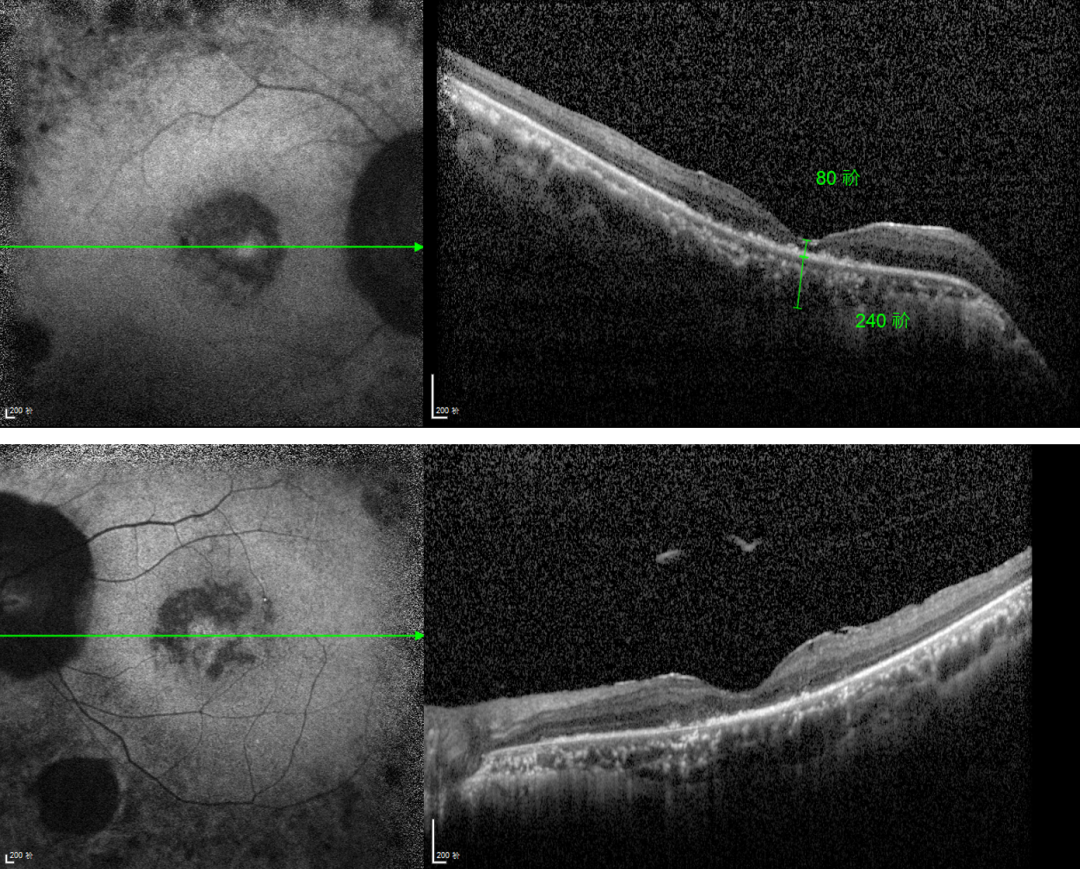

RP的診斷主要依靠眼底檢查、視野檢查、視網(wǎng)膜電圖(ERG)和基因檢測。眼底檢查可見(jiàn)典型的"骨細胞樣"色素沉著(zhù),ERG顯示視網(wǎng)膜功能下降,基因檢測可確定具體的突變基因。

視網(wǎng)膜色素變性